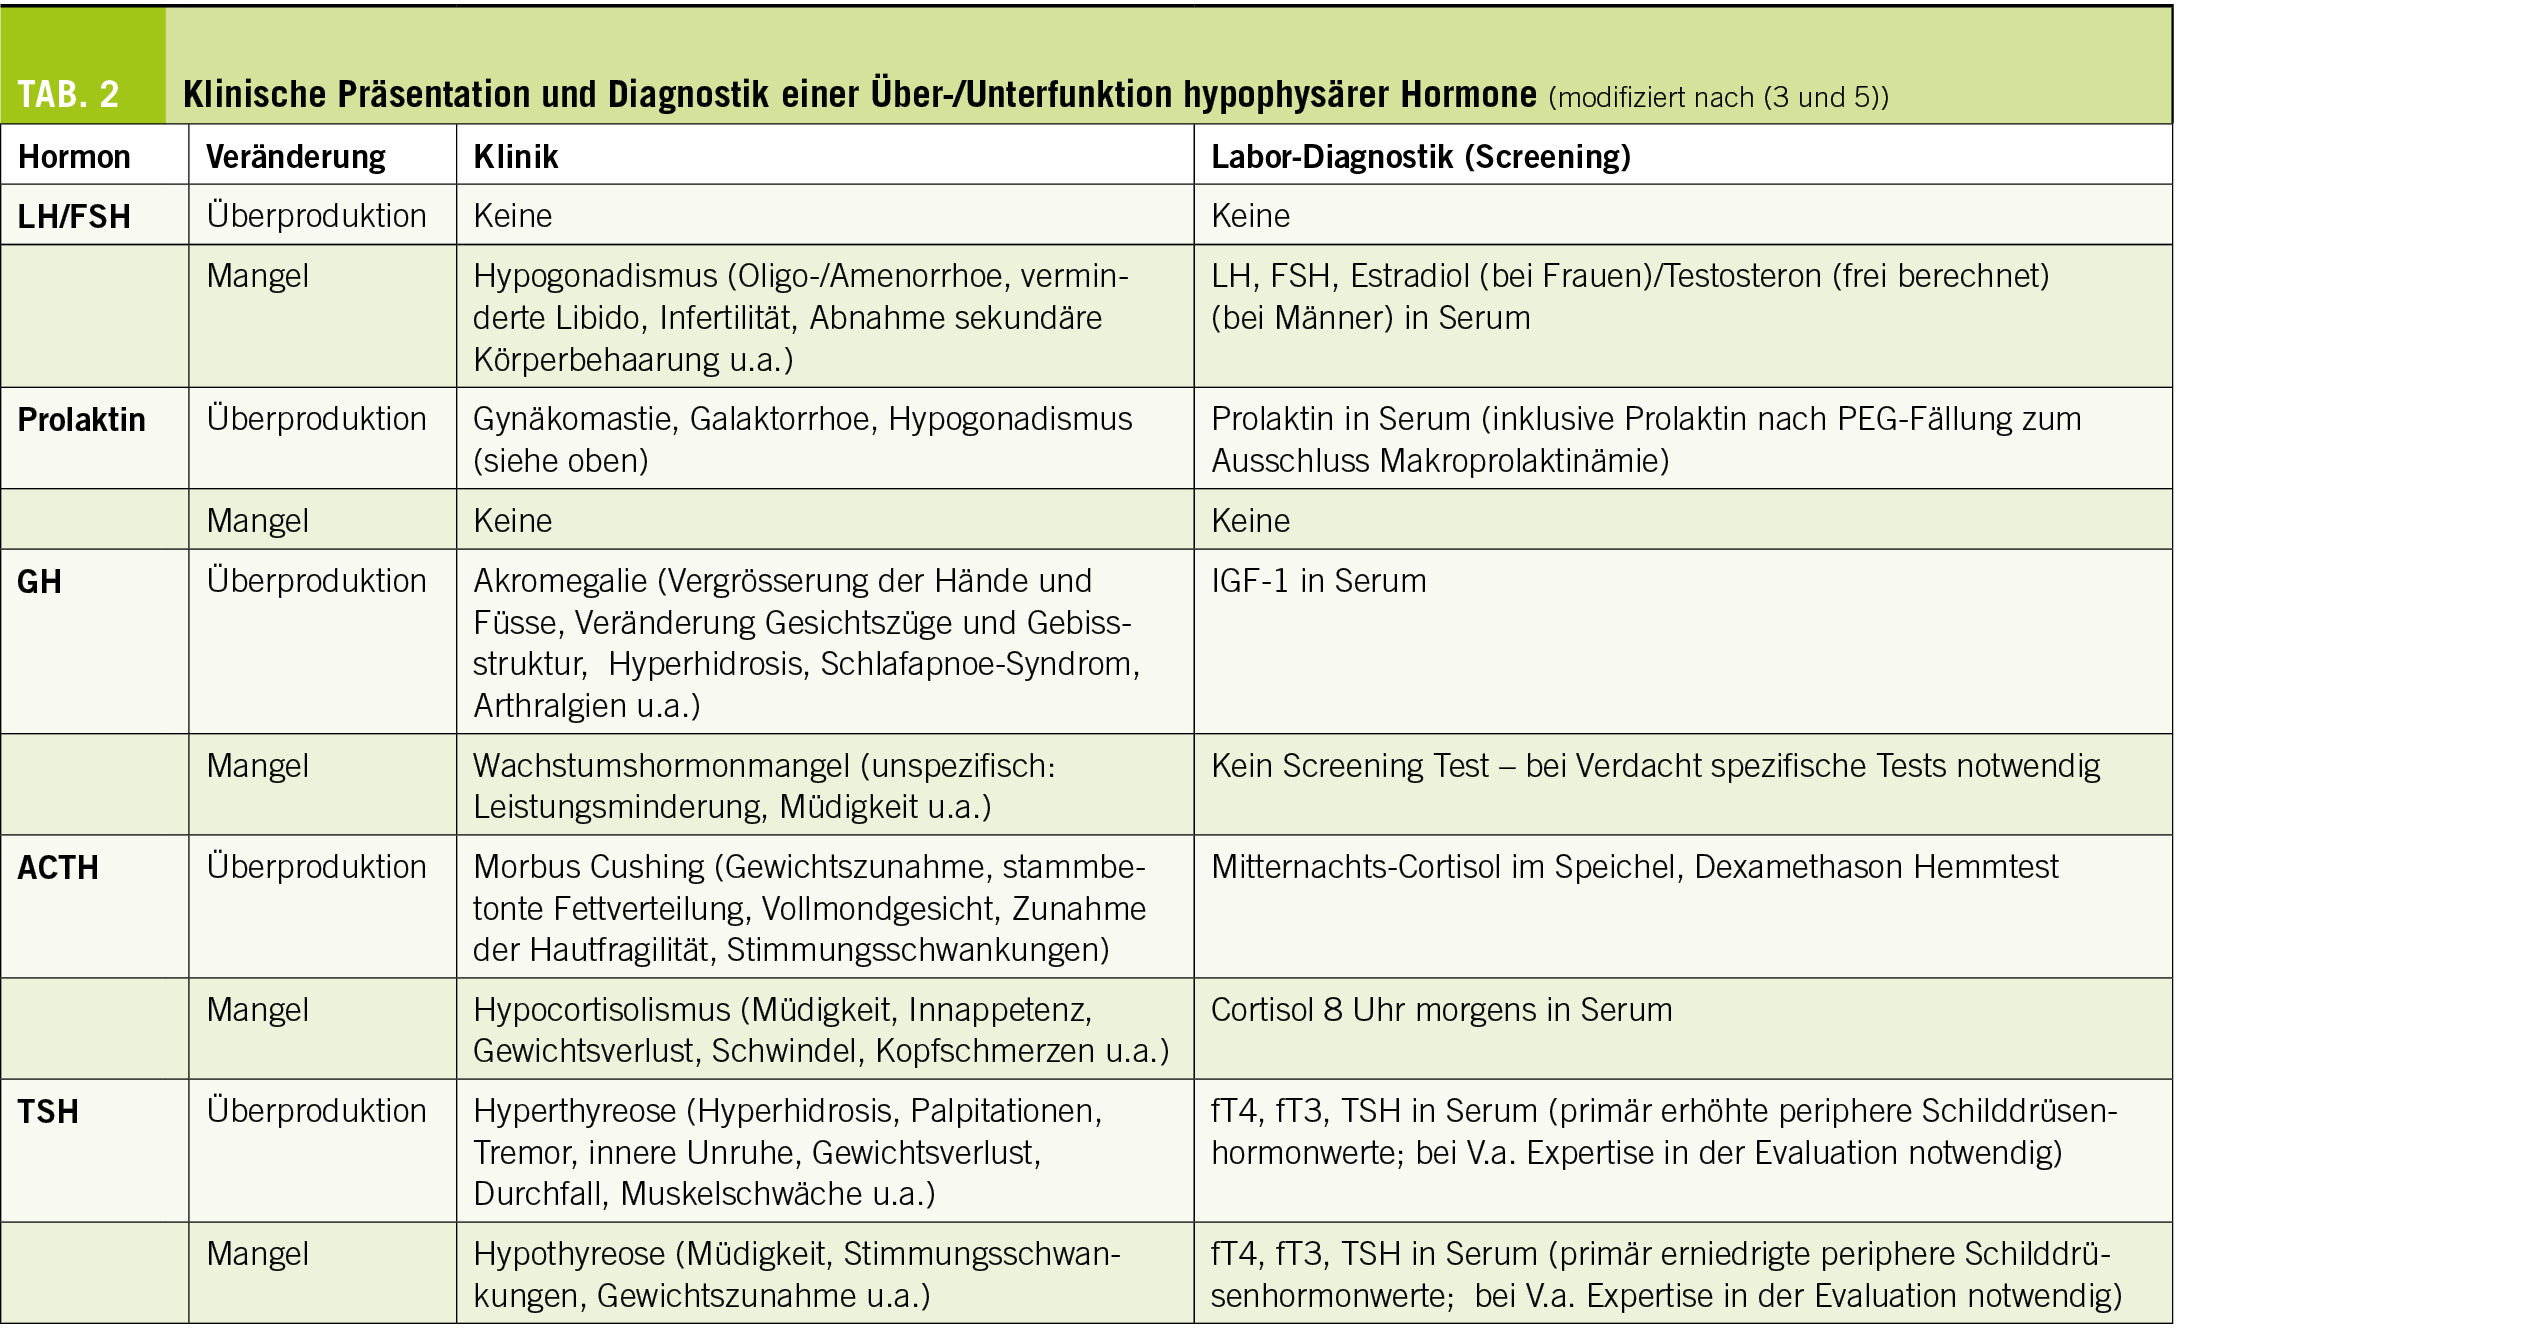

Ein weiterer Bestandteil der initialen Evaluation ist die endokrinologische Aufarbeitung (Tab. 2) (2, 3, 5). Eine fachspezifische Anamnese, klinische Untersuchung sowie adäquate Laboranalyse, bei Bedarf mit dynamischer Testung (Funktionstests), sind notwendig um eine Übersekretion oder einen Mangel der hypophysären Hormone festzustellen bzw. auszuschliessen.

Während die vollständige Untersuchung nach Hormonhypersekretionen nur bei Adenom-verdächtigen Läsionen vorgenommen werden sollte, soll die Bestimmung des Prolaktins bei jeder Raumforderung erfolgen.

Eine Hyperprolaktinämie kann in diesen Fällen zwei verschiedenen Ursachen haben. Einerseits kann eine autonome Prolaktin Sekretion durch ein Hypohysenadenom (Prolaktinom) bedingt sein. Andererseits kann das durch eine kompressions-bedingte fehlende physiologische Hemmung der Prolaktinsekretion (die dopaminerge Innervation, welche für die Hemmung der Prolaktinsekretion notwendig ist, verläuft von Hypothalamus ausgehend durch den Hypophysenstiel zu den Prolaktin-sezernierenden Zellen der Hypophyse) zu einer sogenannten «Enthemmungs-Hyperprolaktinämie» kommen. Dies wird auch «Stiel-Effekt» genannt. Die Prävalenz der hormonaktiven Adenome liegt zwischen 0.04 bis 1 pro 1000 Patienten, wobei eine Enthemmungs-Hyperprolaktinämie in bis zu 15% bei Vorliegen von Makroinzidentalomen beschrieben wird (2).

Häufiger hingegen und in 10 bis 40% der Fälle beschrieben ist ein zumindest partielles Defizit der hypophysären Hormone. Am häufigsten betrifft dieses die Gonaden-Achse, gefolgt von der thyreotropen, corticotropen und somatotropen Achse (2).